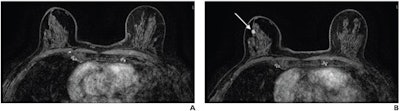

(A) Axial subtracted contrast-enhanced fat-suppressed T1-weighted image from a baseline abbreviated MRI examination is negative (BI-RADS category 1). (B) Axial subtracted contrast-enhanced fat-suppressed T1-weighted image from a subsequent-round abbreviated MRI examination performed two years later shows a new 5-mm enhancing mass in the upper outer right breast (arrow), which was not seen on a mammogram performed five months prior. The exam was assessed as BI-RADS category 5. Ultrasound-guided core biopsy yielded invasive ductal carcinoma (ER+/PR+/HER2-). Image courtesy of the ARRS.